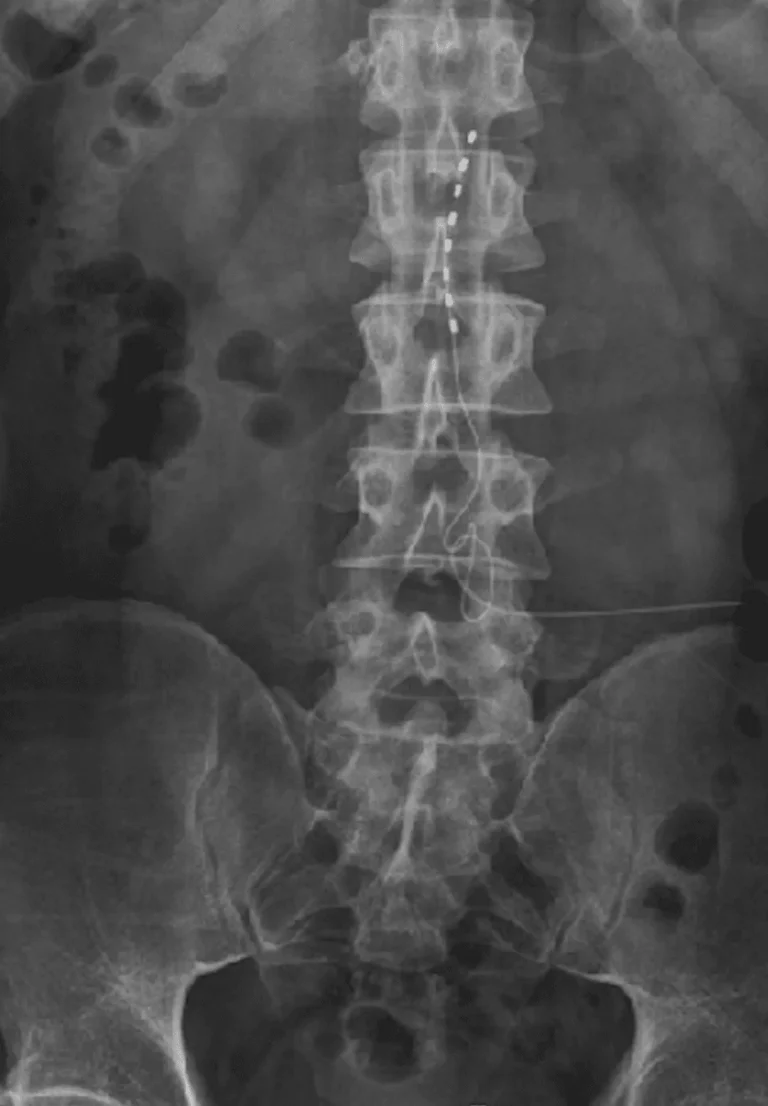

X-ray image showing a spinal cord with a series of electrode implants.

Spinal Instability

X-ray image showing a spinal column with a spinal cord stimulator implant.

Lead Migration

Implanted leads shift from their original position, causing loss of pain relief and requiring revision surgery.